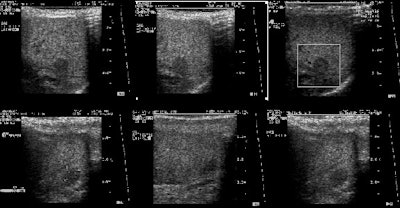

|

Benign adrenal lesion with FDG uptake: The patient shown below had a left adrenal mass which had remained stable for 2 years (white arrow). The stability over time and CT features would be consistent with a benign adrenal lesion- likely an adenoma. Note the marked FDG uptake within the mass on PET imaging (black arrows). Benign adrenal adenomas can accumulate FDG resulting in false positive exams. The use of PET/CT has been shown to improve the specificity of the PET exam. |